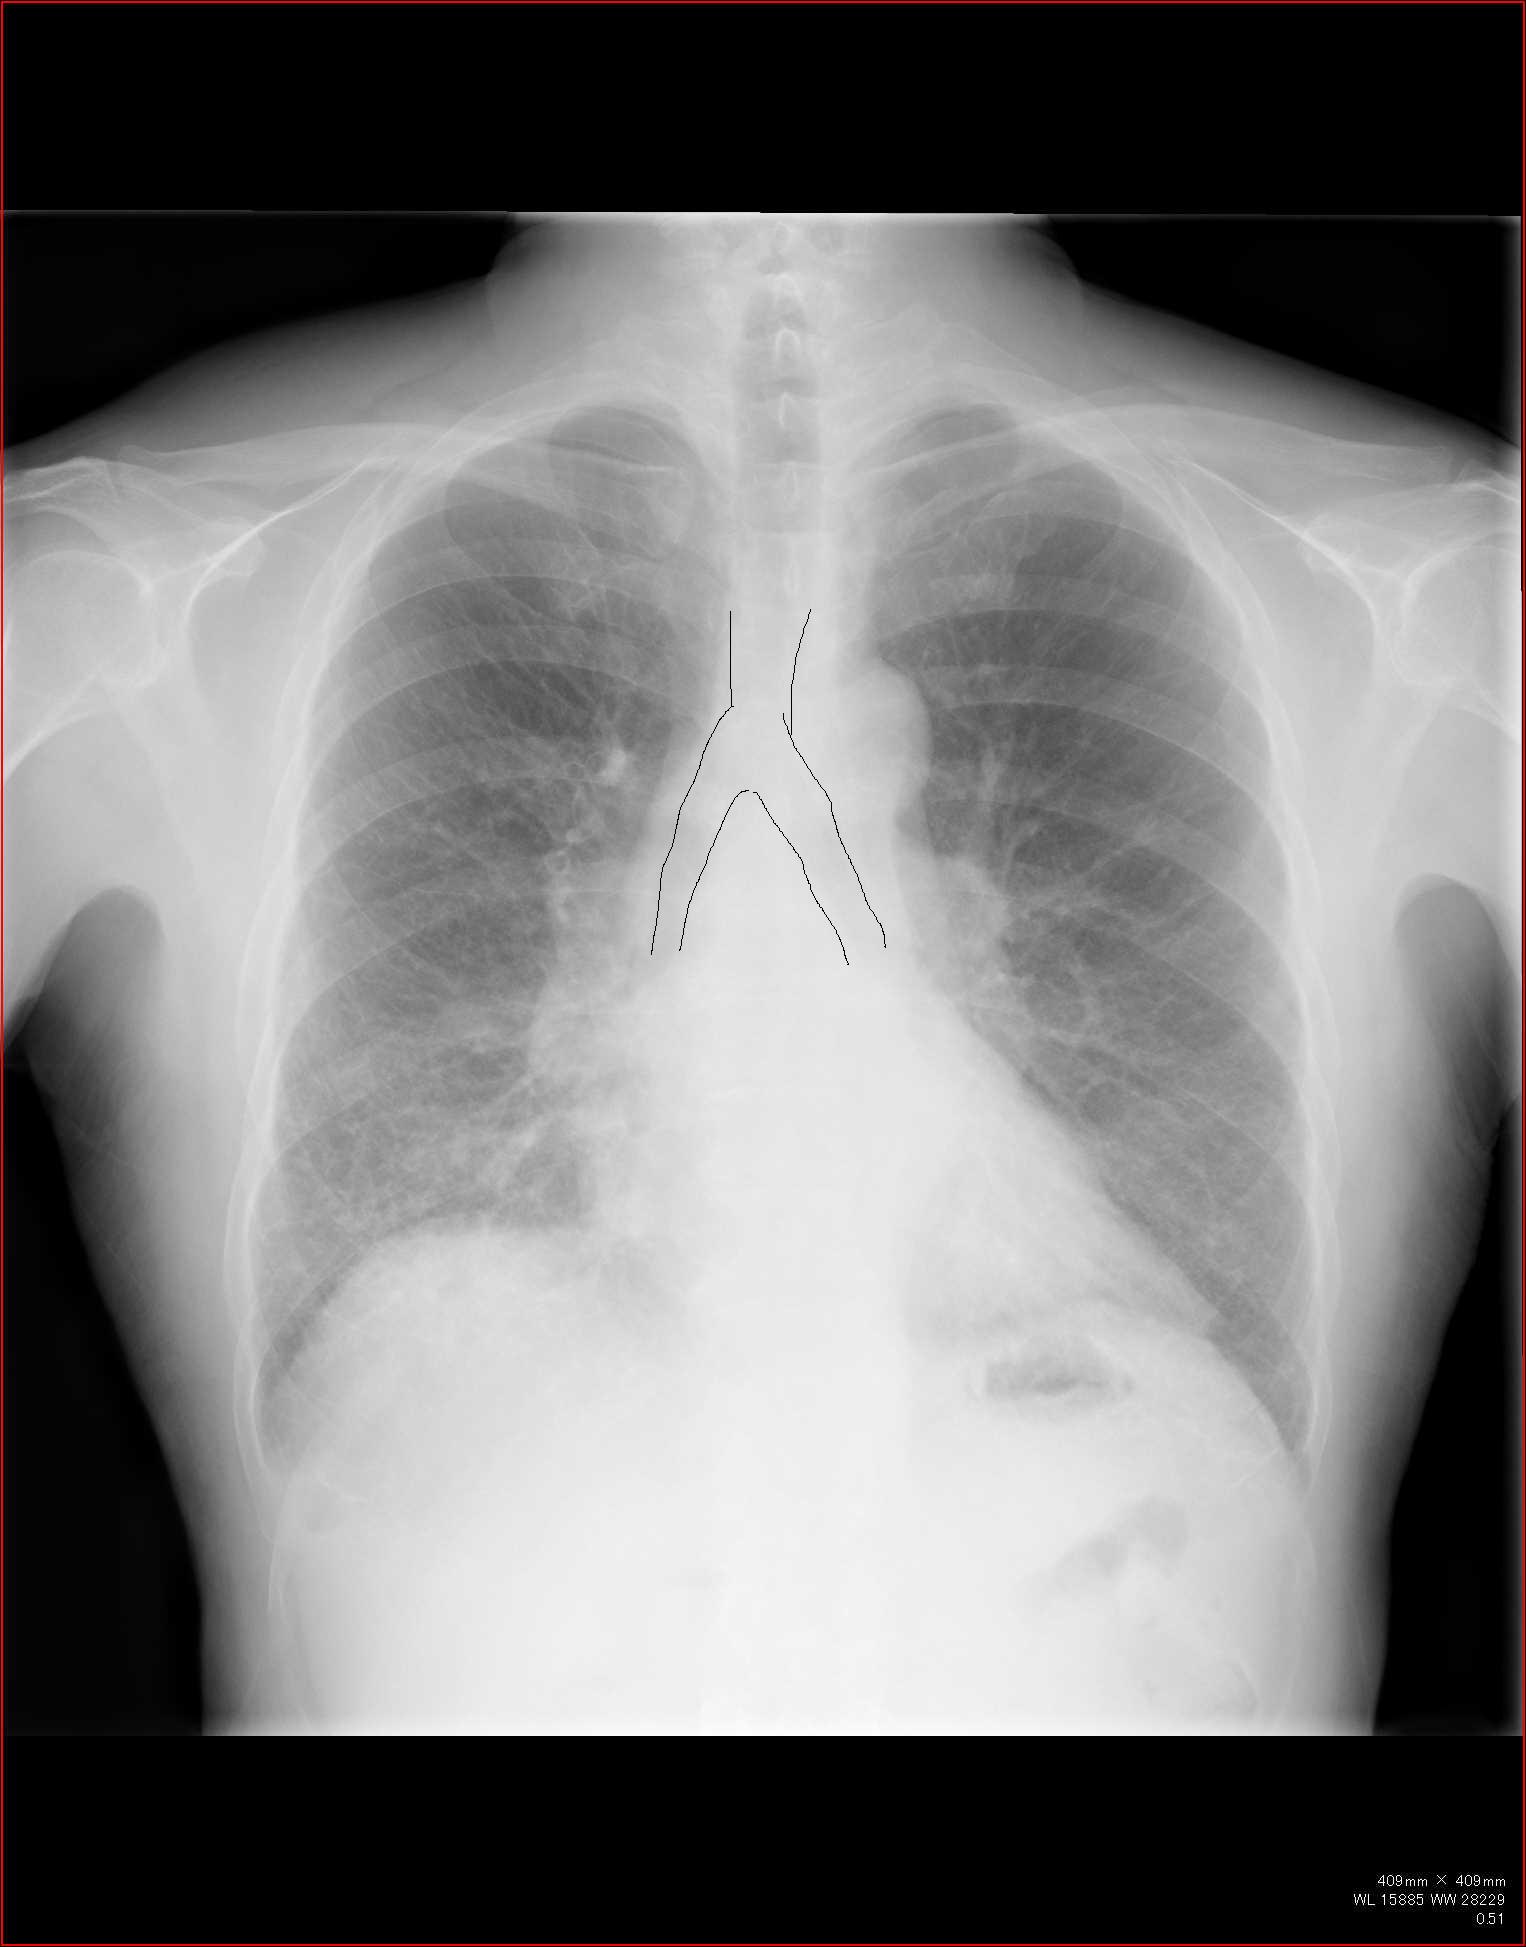

縦隔の所見

縦隔を見るときに、ボーッと見ていては所見を見逃します。

各種の線を追いかけていきましょう。

こちらを見て下さい。

わかりにくいかもしれませんが、このあたり。

気管が追いにくい、無くなっているようにも見えます。

CTで見ると…

3Dだと、こうなります。

気管狭窄ですね。こういう所見もレントゲンで捉えることができるのです。